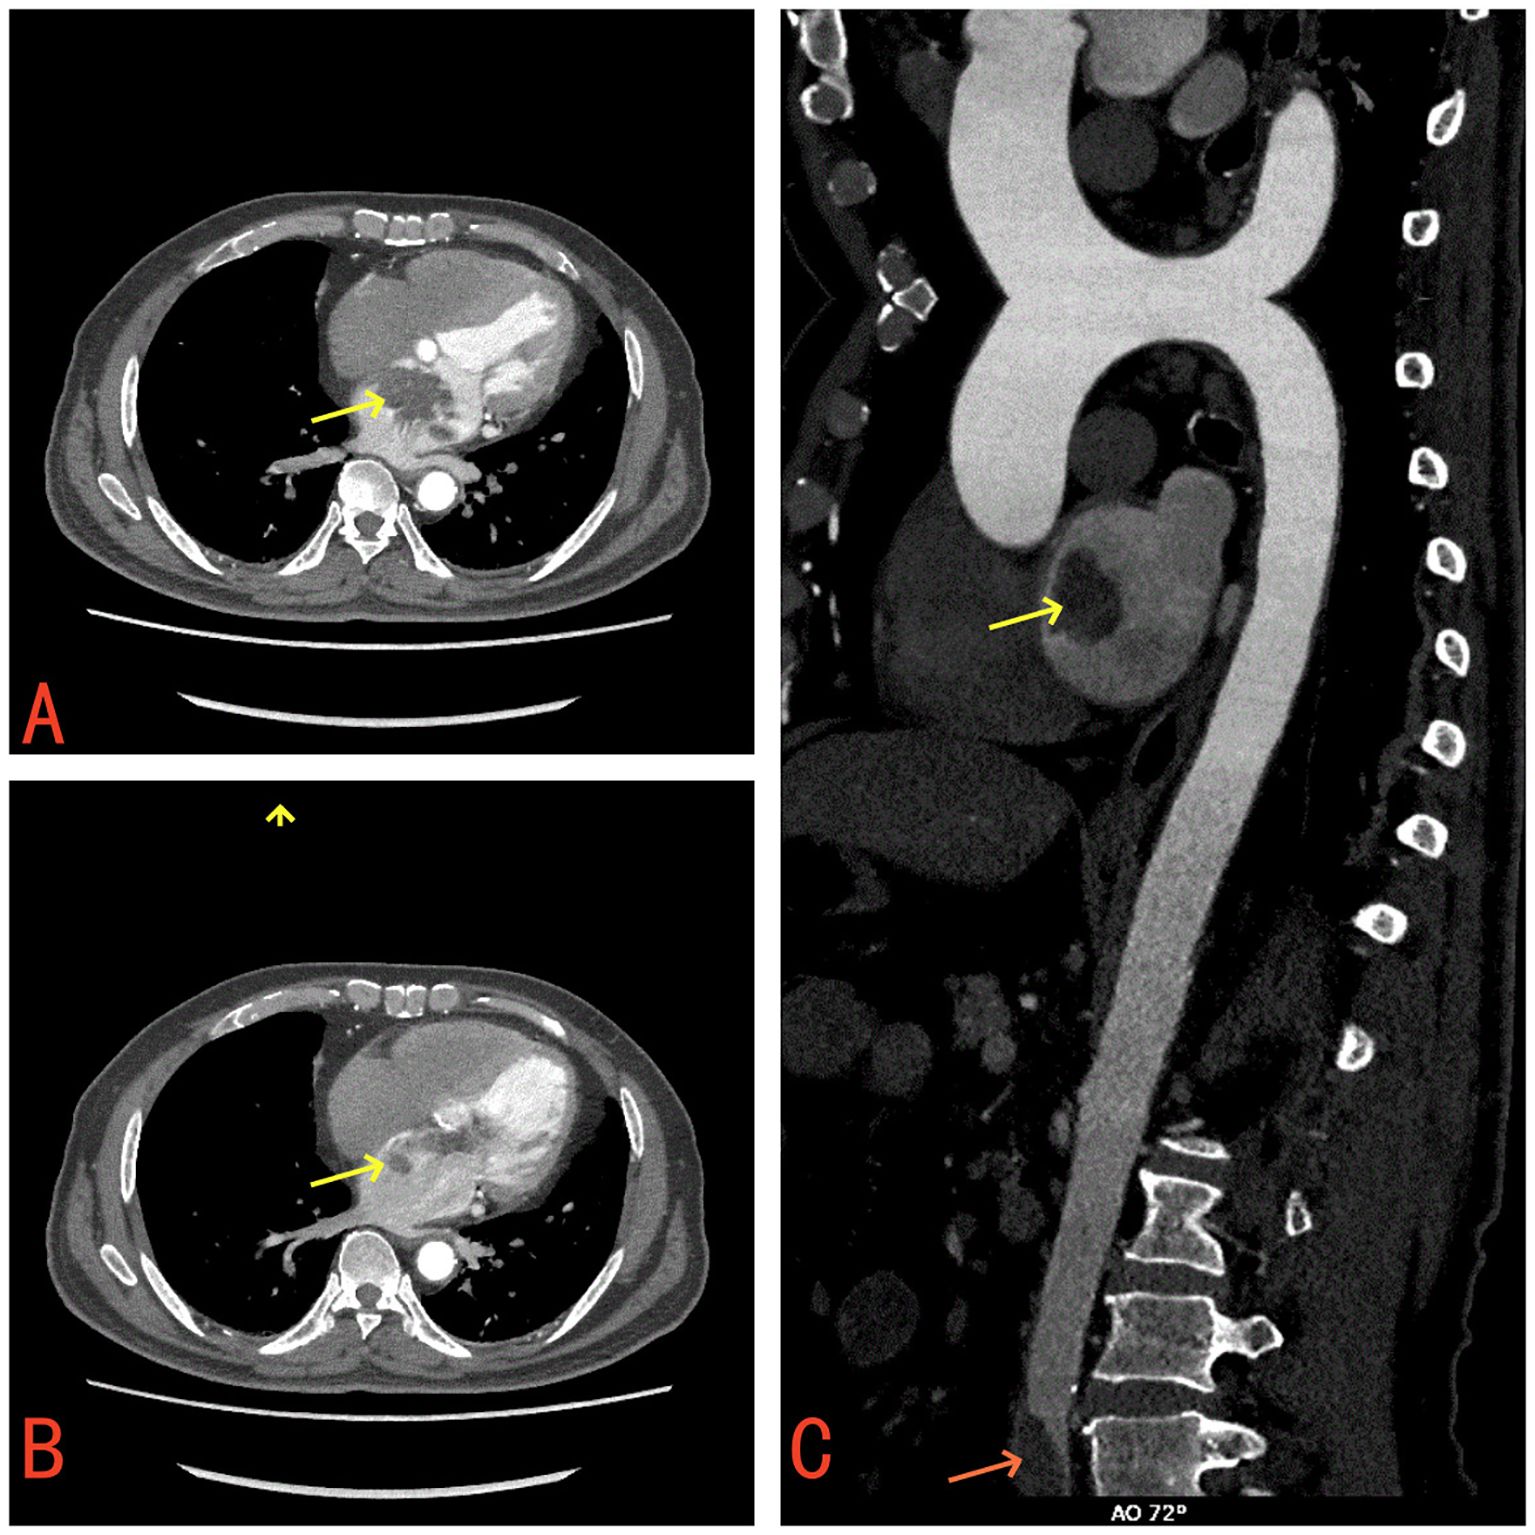

Laboratory tests revealed a raised white blood cell count of 12.58×10^9/L, with 83% polymorphonuclear cells. The hemoglobin concentration was 10.2 g/dL, and the hematocrit was 30.8%. The fasting blood glucose level was 9.73 mmol/L. Serum albumin and C-reactive protein (CRP) levels were 31.7 g/L and 16.10 mg/dL, respectively. Urine analysis showed glucose 2+ and protein 1 +. Chest computed tomography (CT) and electrocardiograms were normal. Aortic and coronary CT angiography (CTA) indicated a space-occupying lesion in the left atrium and a filling defect at the intersection of the abdominal aorta and bilateral common iliac arteries, suggestive of thrombosis (Figure 1). Transthoracic echocardiography (TTE) and TEE revealed an elongated, irregular mass originating from the fossa ovalis in the left atrium, with a base of approximately 9 mm and dimensions of approximately 7 cm × 3 cm. The tumor prolapsed into the left ventricle during diastole, causing mitral valve obstruction. TEE revealed punctate non-shadowing echogenic foci without comet tail artifact on the surface of the tumor (Figure 2; Supplementary Video 1). These findings were consistent with atrial myxoma. Additionally, the echocardiographic findings included left atrial dilation, mild to moderate tricuspid regurgitation, tachycardia, and an estimated ejection fraction of 55% in the left ventricle.

Figure 1. (A) Contrast-enhanced CT demonstrates a mass in the left atrium (yellow arrow). (B) The left atrial mass prolapses through the mitral valve into the left ventricle (yellow arrow). (C) A filling defect suggestive of thrombus observed at the bifurcation of the abdominal aorta and bilateral common iliac arteries (red arrow).